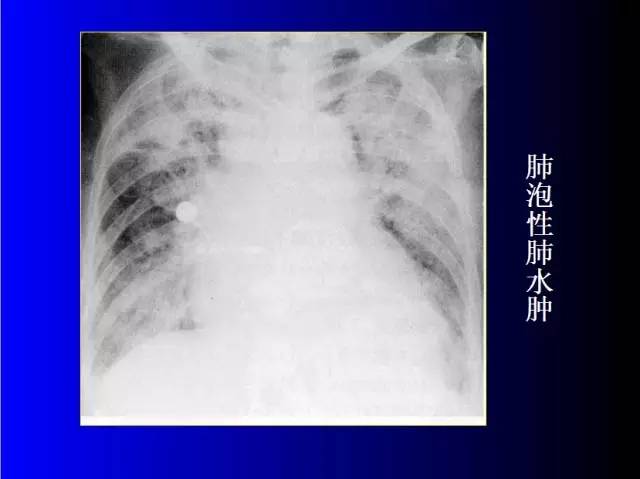

肺部基础X片及CT片解读